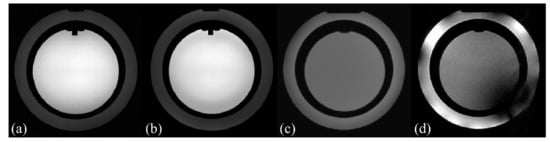

Table 3 and Figure 5a,b list the 1H MR experimental results using the ACR phantom. The PIU of the 1H MR image acquired using body coil transmission and reception was 85.0% for case 1, while it was 83.5% for case 2, which is with the 16-leg 13C PFT birdcage RF coil containing CPSCs. The PIU reduction between cases 1 and 2 was 1.50%. For case 3, the PIU of the 1H MR image using the body coil transmission and reception with the 16-leg 13C birdcage RF coil without CPSCs was not measured due to the excitation failure of the 1H nucleus caused by an unusually low B 1 + intensity.

Figure 5c,d demonstrate the 1H T2-weighted reference MR images of the corn-oil phantom with a 16-leg low-pass PFT 13C birdcage RF coil containing CPSCs and a 16-leg low-pass 13C birdcage RF coil without CPSCs. In Figure 5d, the 1H MR image of corn-oil phantom showed degraded image quality with poor homogeneity compared with Figure 5c.

Figure 5. ACR phantom images using body coil transmission and reception without a PFT 13C birdcage RF coil: (a) and with a PFT 13C birdcage RF coil: (b) in a 3.0 T MRI system, showing almost identical uniformity as (a). 1H MR images of the corn-oil phantom using body coil transmission and reception with a 16-leg low-pass PFT 13C birdcage RF coil with CPSCs: (c) and with a 16-leg low-pass 13C birdcage RF coil without CPSCs: (d) in a 3.0 T MRI system. 1H MR image of corn-oil phantom in (d) shows inhomogeneity compared with (c), which verifies that proposed CPSCs act appropriately for 1H MR imaging.